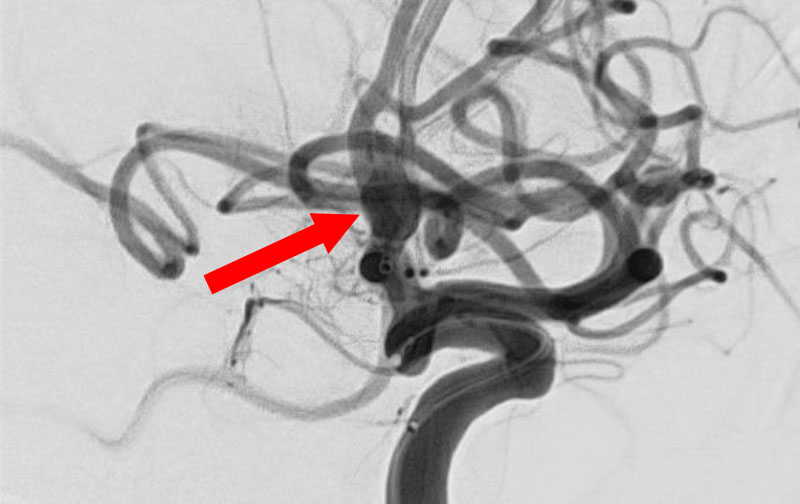

'25年11月

左内頚動脈脳動脈瘤

60代

大阪府の病院

No.1595 手術前